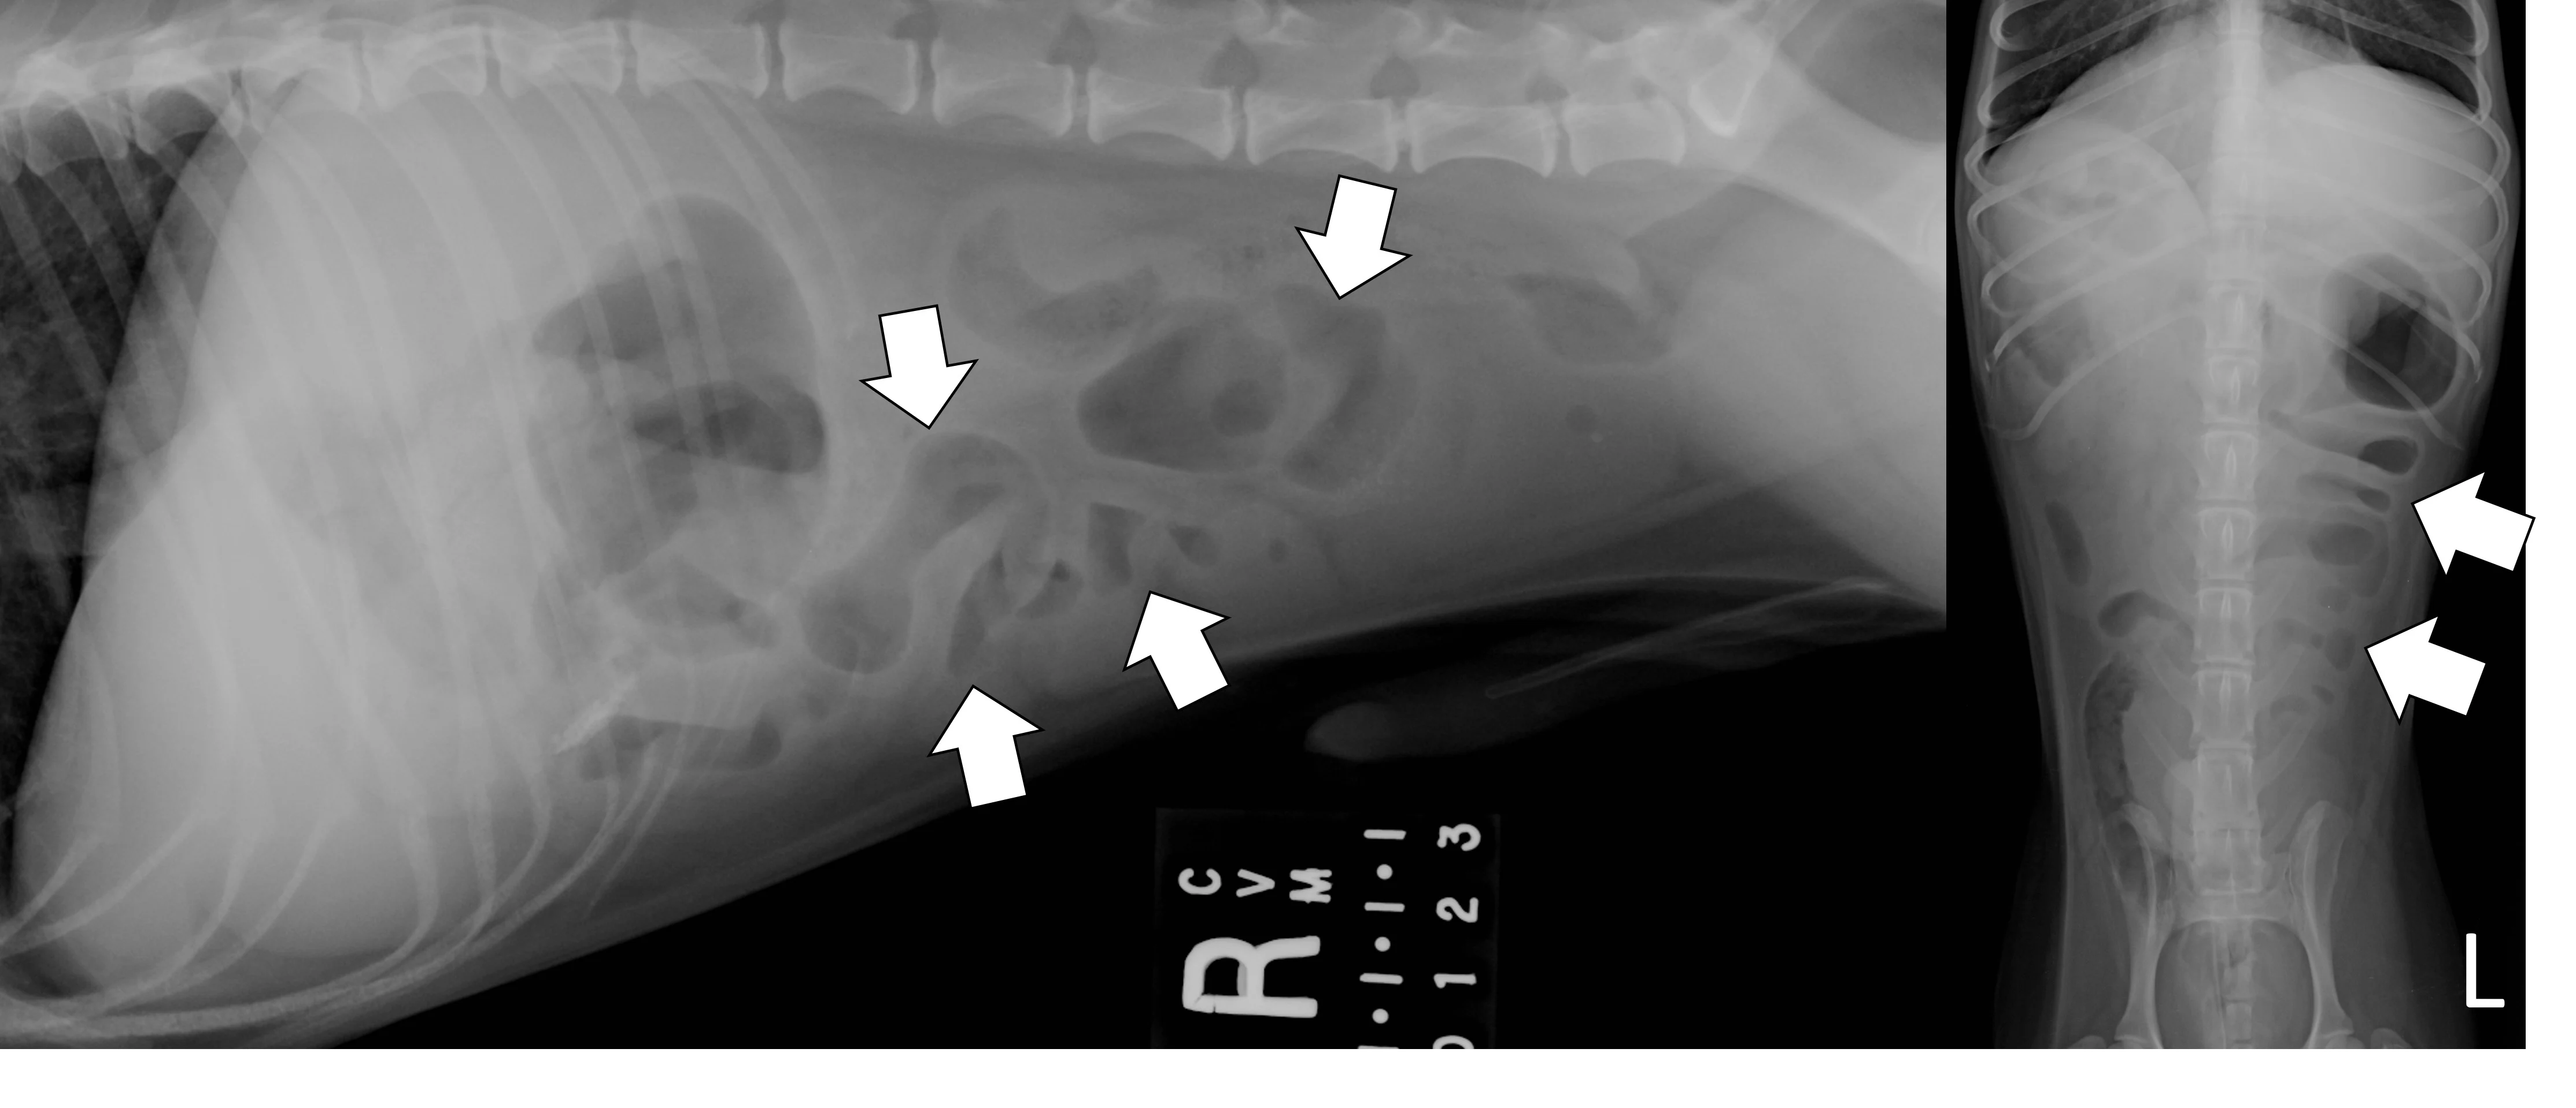

Evaluate the peritoneal space for decreased serosal detail and/or free gas, the combination of which strongly suggests septic peritonitis secondary to GI perforation (Figure 2).

Right lateral and ventrodorsal abdominal radiographs of a 10-month-old neutered male pit bull with a small intestinal mechanical obstruction of undetermined etiology. The stomach is moderately dilated with fluid and gas (pound signs), and there is moderate segmental dilation of the small bowel with stacking and hairpin turns (asterisks). Peritoneal serosal detail is diffusely decreased with a small, tear-drop–shaped intraperitoneal gas bubble between the liver and stomach (arrow) consistent with septic peritonitis secondary to presumed GI perforation.

Small intestinal mechanical obstructions occur when a foreign body blocks the lumen of any segment of the small bowel, causing segmental dilation located orad to the foreign body. As the small bowel increases in size, it becomes crowded in the peritoneal space and begins stacking on itself with sharp, hairpin turns (Figure 4).1 Dilated portions of the small bowel usually contain a mixture of fluid and gas. Occasionally, intraluminal gas may outline part of a foreign body, making the object easier to see. Although the diameter of the small intestine can be objectively measured and compared with the height of the center of the L5 vertebral body,6,7 one study found that using the small intestinal diameter:vertebral body height ratio did not increase the diagnostic accuracy for mechanical obstruction on radiographs regardless of clinician experience.8

Right lateral and ventrodorsal abdominal radiographs of a 1-year-old neutered male domestic shorthair cat with a small intestinal mechanical obstruction from a surgically confirmed earplug lodged in the distal jejunum. The stomach is mildly dilated with fluid and gas (pound signs). Segmental fluid and gas dilation of the small bowel with stacking and hairpin turns can be seen (asterisks). On the ventrodorsal projection, intraluminal gas outlines the margin of the earplug (arrow).